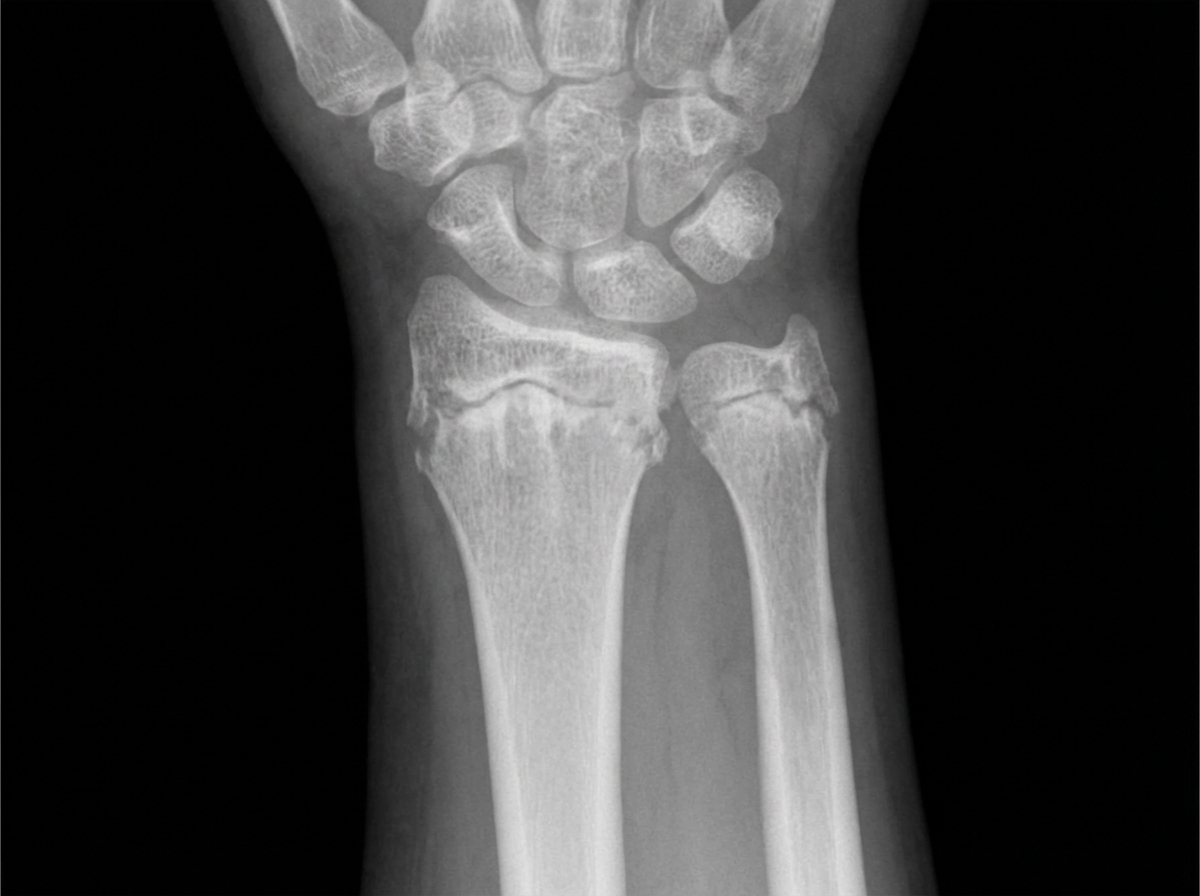

The following X-ray is diagnostic of:

Explanation: ***Rickets*** - Classic X-ray findings include **metaphyseal cupping**, **fraying**, and **widening of the growth plate** due to defective mineralization of the growth plate cartilage. - **Coxa vara**, **bowing deformities** of long bones, and **delayed ossification** are characteristic features that make this diagnosis evident on radiographs. *Scurvy* - X-ray shows **Frankel's line** (dense metaphyseal line), **Pelkan spurs** (corner fractures), and **Trümmerfeld zone** (rarefied metaphyseal area). - Caused by **vitamin C deficiency** affecting collagen synthesis, not calcium metabolism like rickets. *Hairline fracture of radius and ulna* - Would appear as **thin lucent lines** through the cortical bone without affecting the growth plates or causing metaphyseal changes. - **Acute trauma history** would be present, and there would be no generalized bone deformities or growth plate abnormalities. *Osteopetrosis* - X-ray shows **increased bone density** with a **marble bone appearance** and **sclerotic changes** throughout the skeleton. - **Erlenmeyer flask deformity** and **bone-in-bone appearance** are characteristic, opposite to the osteopenic changes seen in rickets.